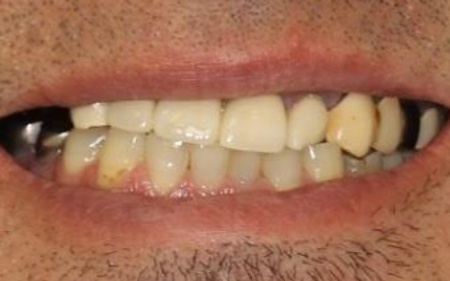

治療前

治療後